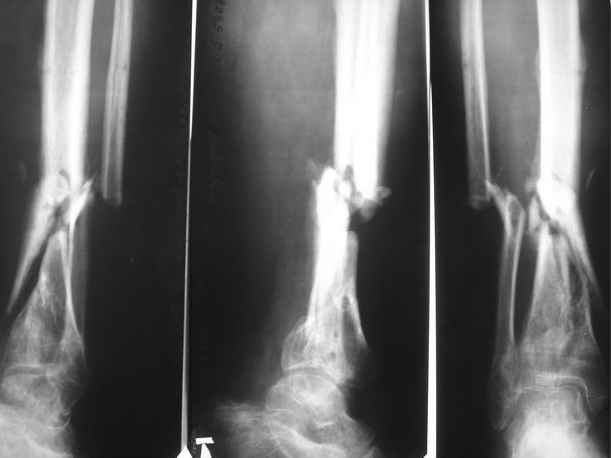

Здравствуйте, уважаемые коллеги. Хотелось бы услышать ваше мнение по следующему случаю: Пациент 35 лет, травма в декабре 2007 г. Открытый оскольчатый перелом костей левой голени в нижней трети со смещением отломков. Травма в результате ДТП. В этот же день выполнена ПХО открытого перелома костей левой голени, скелетное вытяжение. На 3 день ЧКДО с учетом повреждения мягких тканей. Посттравматический период осложнился обширным циркулярным некрозом кожи. Через этапные некроэктомии, и свободную кожную пластику раны зажили вторичным натяжением. По заживлении мягких тканей перемонтаж аппарата. Выписан на амбулаторное лечение. В августе 2008 г. из за выраженного воспаления в местах выхода спиц, аппарат демонтирован. Явления воспаления купированы. Данных за остеомиелит не получено. На данный момент имеем: ложный сустав левой большеберцовой кости в нижней трети. Укорочение левой нижней конечности на 3 см. Комбинированная контрактура левого голеностопного сустава. Клинически – патологическая подвижность в области перелома. Лабораторные показатели в пределах нормы. Местно воспалительных явлений мягких тканей нет. Планы: 1. Вариант № 1(основной) – в два этапа. 1. Наложить спице-стержневой аппарат, за 5 – 7 – 10 дней устранить смещение отломков (восстановить ось большеберцовой кости). 2 этап закрытый блокированный остеосинтез цельным гвоздем диметра 10 – 11 мм для низких переломов голени (Эксперт, Мастер…). Сначала в статику на 2-3 недели, затем динамизацию. Вопрос: 1.Достаточна ли длина дистального отломка для жесткой фиксации на гвозде ( как минимум на 3 винтах)? 2. Как будут проходить гибкие риммеры через область ложного сустава при рассверливании костно – мозгового канала? 3. Возможно ли выполнить закрытый блокируемый остеосинтез без предварительного наложения КДА? 4. Где могут быть технические трудности?

В принципе. да, но не было ли это переломом пилона, что-то сейчас с суставом неладно. Есть ли более ранние снимки? А то, может, есть смысл сделать сразу и артродез голеностопного сустава.

Вы обсолютно правы - линия перелома на первичных снимках доходила до сустава

Даже на рентгенограммах видно, что ложный сустав имеет аваскулярный, гипопластический характер. Жизнеспособность свободнолежащего осколка тоже вызывает сомнения, скорее всего это некрост, что может быть подтверждено компьютерной томографией (она кстати будет полезна и при планировании закрытого "штифтования", так как на поперечных срезах вы увидите состояние костномозгового канала и оцените возможность закрытого проведения штифта). Более правильной представляется позиция доктора Lespovich. Введение в зону аваскулярного ложного сустава остеоиндуктивного материала необходимо. Либо пересадка, либо резекция концов сустава. Остекондуктивный материал и фиксация могут не сработать. Плюс имеется укорочение ноги и фиброзный анкилоз, кторые на штифте вы не вылечите.